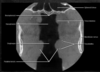

what is this xray of

base of skull

104

airway